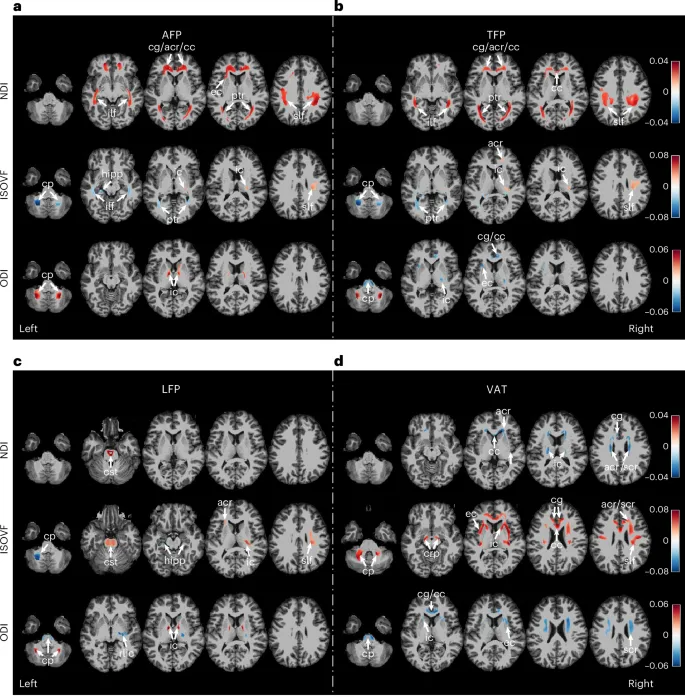

Методы оценки ожирения и здоровья мозга

Для testing этого, мы использовали dual-energy X-ray absorptiometry (DXA) для quantification ожирения в arms, trunk, legs и VAT. Здоровье мозга evaluated через multimodal imaging, включая measures morphology мозга, FC и microstructure белого вещества. Мы также applied модели prediction возраста мозга для estimation system-specific brain age gaps (BAGs), providing insights о том, как различные brain networks могут быть differentially affected ожирением.

Результаты исследования

Анализы revealed, что ожирение в arm, trunk, leg и visceral regions было differentially ассоциировано с metrics визуализации мозга, с spatial patterns, преимущественно involving subcortical–cerebellar–brainstem, sensorimotor, limbic и default mode systems. Важно, что эти associations были independent от общего ожирения, так как каждый measure регионального ожирения был statistically modeled чтобы exclude variance, shared с ИМТ.

Среди всех measures регионального ожирения, visceral adiposity demonstrated самые сильные negative associations с как integrity мозга, так и cognitive function, highlighting его potential роль как critical marker obesity-related neurocognitive risk. Хотя ИМТ остается наиболее widely used index ожирения, он часто obscures distinct contributions распределения жира к health outcomes.

Мозговые системы, наиболее уязвимые к ожирению

В present study, четыре brain systems, включая subcortical–cerebellar–brainstem, sensorimotor, limbic и default mode systems, были наиболее commonly implicated в relation к региональному ожирению. Эти systems known to support homeostatic regulation, motor control, emotional processing и self-referential cognition, и frequently involved в obesity-related neural alterations.

Различия в воздействии на разные области мозга

Ожирение в arm и trunk showed более pronounced associations с cortical thinning в sensorimotor cortex compared к leg и visceral regions. Этот pattern aligns с earlier evidence, suggesting что upper-body ожирение может exert greater metabolic и cardiovascular burden чем lower-body ожирение. Важно, что sensorimotor cortex vulnerable к age-related atrophy, который может быть partly attributable к его high metabolic activity.